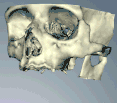

Методы, используемые для планирования имплантатов